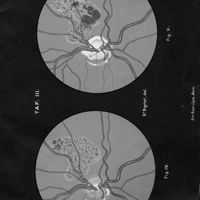

Ophthalmoskopische Studien

- Ophthalmoskopische Studien

- Mitteilungen aus kliniken und medicinischen Instituten der Schweiz, Vol. 3, pp. 545-82

- Siegrist - Hutchinson (syndrome de)